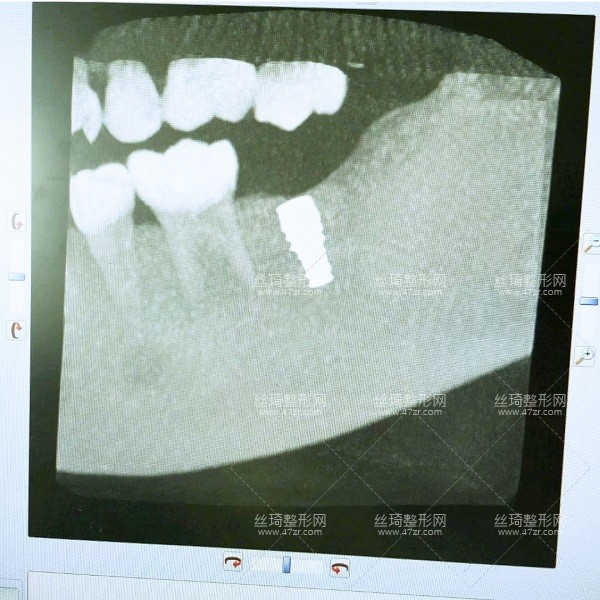

2.種植牙案例

手術(shù)第1天

一直不知道什么原因?qū)е挛业难罆?huì)這樣,多方咨詢之后選擇了長(zhǎng)沙中諾口腔進(jìn)行整牙,過去檢查了一下,醫(yī)生說我可以搞種植牙,但是以前補(bǔ)過的牙現(xiàn)在顏色變了,需要重新做,看來是個(gè)大工程啊,啊啊啊啊~~~

手術(shù)第2天

今天過來醫(yī)生檢查了我的牙床和骨組織,情況不錯(cuò),可以直接調(diào)節(jié)。首先助理幫我清潔口腔,護(hù)士準(zhǔn)備手術(shù)室,清理過口腔后,吃了止痛藥,然后進(jìn)手術(shù)室,然后躺到牙椅上,就打麻藥的時(shí)候有點(diǎn)緊張,種牙很輕松,全程一個(gè)半小時(shí)。出來后,冰敷了,告訴我注意事項(xiàng),讓我一周后來拆線。

手術(shù)第8天

較近刷視頻看到很多美食,但是現(xiàn)在與我無緣啊,多么痛的領(lǐng)悟~今天拆線,然后看看后面的牙啥時(shí)候弄。牙醫(yī)說我恢復(fù)的不錯(cuò),但還是要養(yǎng),下周再過來檢查牙周,種植牙的牙冠要等那個(gè)釘修復(fù)好了再帶,要好幾個(gè)月,今天就到這里。